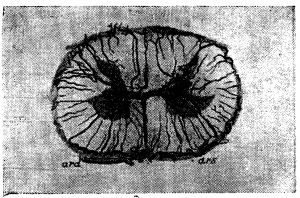

Вены вещества спинного мозга (рис. 1). Центральные вены, подобно артериям, бывают правые и левые, то есть выносят кровь из (какой-либо одной половины серого вещества. В отличие от соответствующих артерий, они анастомозируюг между собой. Возникают они из мелких веточек, близких по калибру к артериолам, и сами являются очень мелкими тканевыми сосудиками. Поллак отмечает, что в сером веществе спинного мозга очень редко встречаются относительно более крупные венозные сосуды: мелкие веточки почти непосредственно собираются, в относительно крупный стволик центральной вены. Центральные вены впадают в передние венозные тракты или вернее они образуют их. Вены белого вещества спинного мозга крупнее соответствующих артериол и центральных вен (вен серого вещества). В отличие от артерий вены серого и белого вещества богато анастомозируют между собой, так что кровь из серого вещества может изливаться двумя путям: через передние и через боковые и задние тракты, чем и объясняется относительно малый калибр вен серого вещества и кажущееся нарушение правила о превосходстве площади сечения вен над площадью сечения соответствующих артерий.

Кадый считает, что центральных вен в два раза больше, чем соответствующих артерий, но калибр ш меньше калибра артерий, так что, по вычислению Кадыя, общая сумма площадей сечения вен на 1/30 меньше суммы площадей сечения соответствующих артерий.

Александер разделяет сосуды вещества спинного мозга на несколько калибров и отмечает, что в поясничной области артериолы и венолы вещества мозга располагаются поперечно оси органа, в грудной — параллельно, а в шейной области расположение сосудов является средним между двумя крайними типами. Автор подчёркивает значение этого анатомического факта для распределения размягчений в спинном мозгу в случаях тромбоза сосудов и нарушения их при хирургическом вмешательстве.

Вены белого вещества спинного мозга или периферические вены выходят на поверхность органа по линии передних и задних корешков, а; также по задней (борозде и образуют на поверхности сложное сплетение, стоящее в центре нашего внимания.